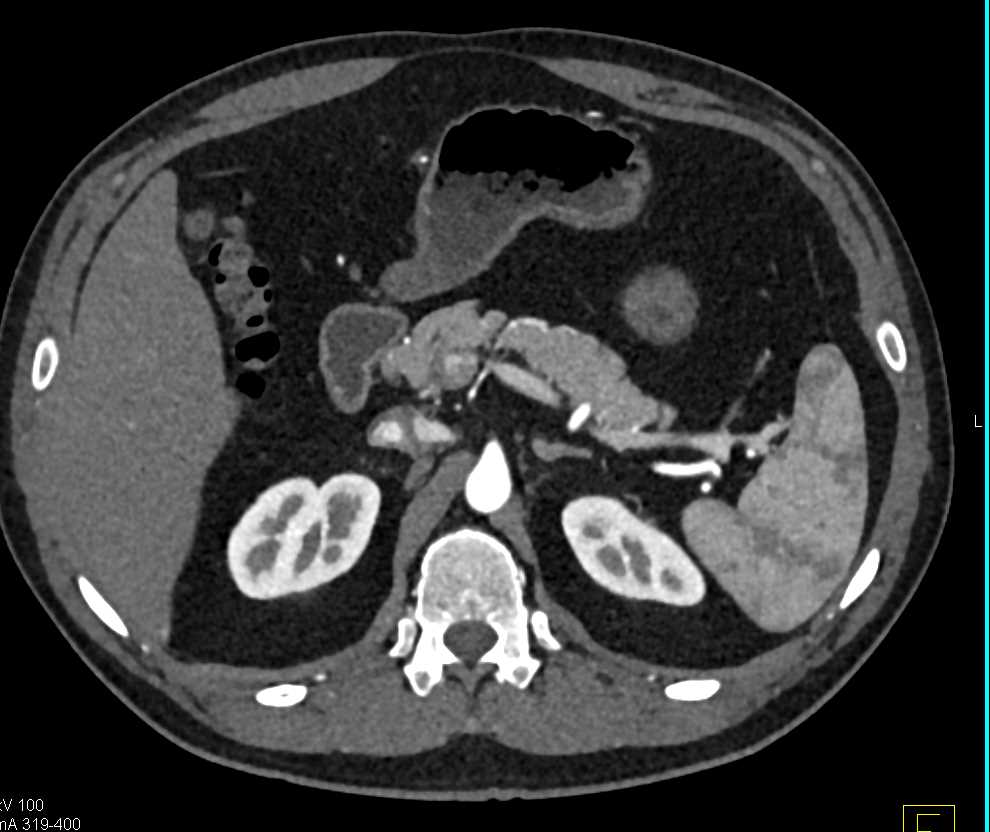

Neuroendocrine Tumor Body of Pancreas